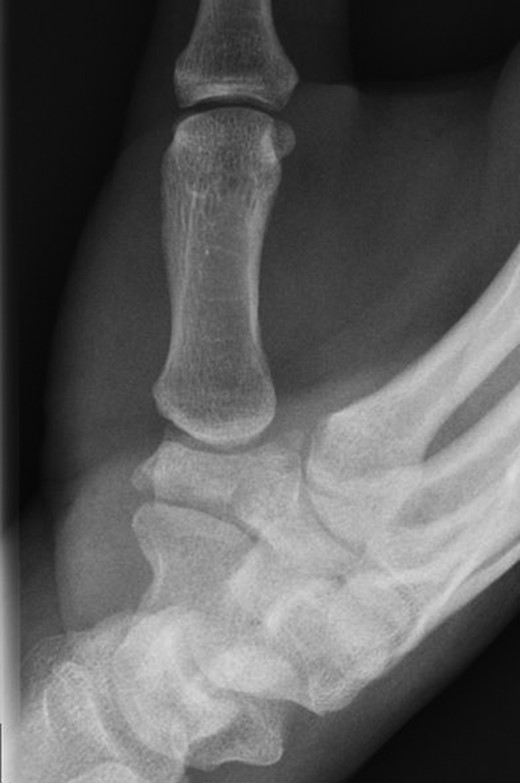

A 49-year-old man fell from his mountain bike at speed and presented to his local secondary care hospital with an injury to the base of his left thumb. There was pain and swelling at the base of the thumb with painful restriction of movements. Initial radiographs were deemed to be normal and he was treated as a soft tissue injury with a period of immobilization followed by physiotherapy. The patient was referred to us four months later as the pain and weakness were persisting. A thorough retrospective perusal of his history and imaging to date was carried out. A review of his initial plain radiographs (Fig. 1) and MRI scans indicated a fracture of the left trapezium and a CT scan was obtained to further characterize the anatomy of the fracture.

The CT scan (Fig. 2) showed a coronal fracture of the trapezium which was not united. At this stage the symptoms of pain and instability continued to persist and were preventing him returning to mountain biking. As the imaging also showed that there were no degenerative changes in either the trapezio-metacarpal joint or the scapho-trapezial joint, the decision was made to proceed with debridement of the non-union and rigid internal fixation.